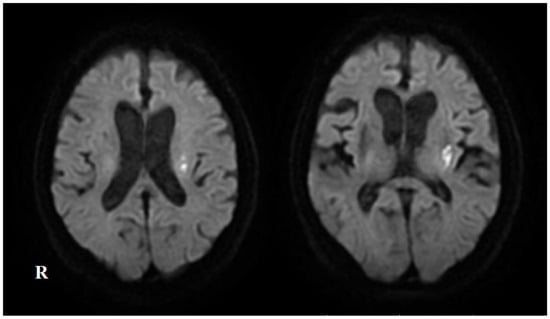

2. Case Presentation